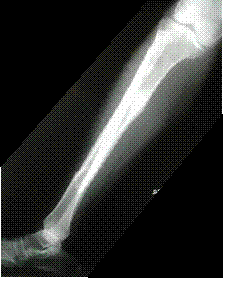

Note the orientation of

the knee joint, then note

the orientation of the

ankle